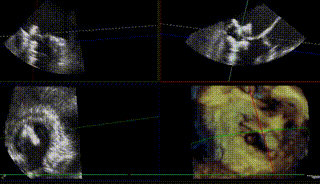

图8-10. 由于反流偏3区,需在MultiVue指导下进行瓣叶捕获夹合,先植入偏3区的夹子后,再次跨瓣植入偏2区的第二枚夹子,二夹收紧后即刻可见反流降至轻度

图11. 二夹解离后3D心房观